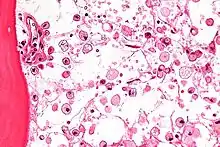

Micrograph of Gaucher disease, with cells that have the characteristic crumpled tissue paper-like cytoplasm. H&E stain.